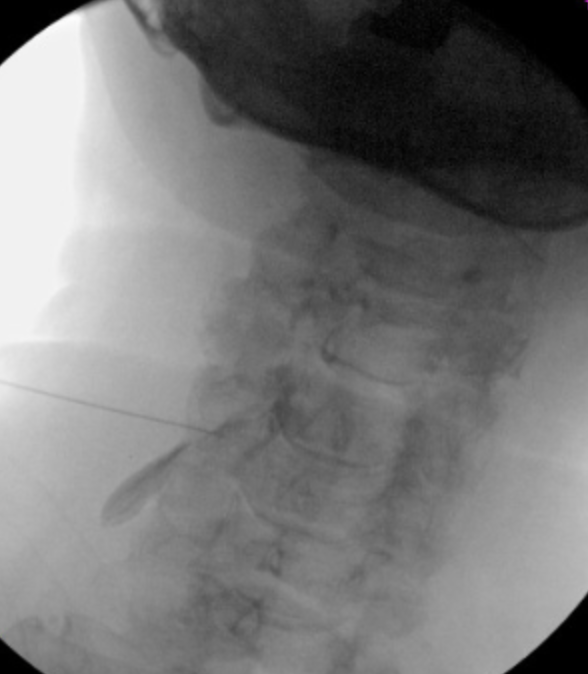

I went Caudal tilt until I saw disc space (**For a cervical Transforaminal)

55 Oblique, till I saw SAP. Hit SAP, walked off, took AP (lateral to unicnate process)

Made sure pre-op MRI that vert was not in way.

Few questions

- The EJ is often right where I wanted to go. has anyone found this to be problem?

- Critique above pics please. Thanks!

Looks good. Poking EJ not the worst thing, though 5 deg more/less of oblique still probably gives you a good trajectory and off the EJ. Def no more medial.

Nice job. I try to avoid all vasculature. If you look at your MRI, superficial vessels will be in the way. Try not to penetrate internal carotid, need to look at more than the vertebral artery alone IMO. Reviewing MRI and measuring planned trajectories, there have been a number of times IC in the way, especially upper cervical. Need to be able to identify. For those cases I use a modified lateral approach. Use small gauge needles. What size needle is that by the way? Looks 22 in oblique but 25 in AP.

25 2.5